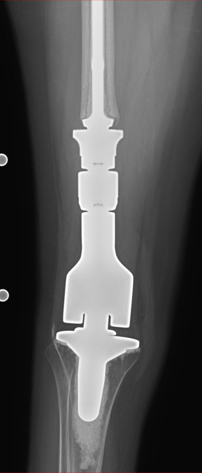

Case: 35 yo F w/ hx of osteosarcoma with painful right DFR. Progressive RLL about femoral stem. Reconstructive options? How to achieve fixation of femoral component?

Reconstructive options include revision DFR, AKA +/- osseointegrated prosthesis, or rotationplasty. After extensive discussion, rotationplasty selected in this case!